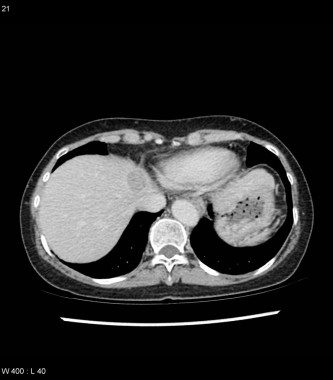

CHC phase tardive

Case courtesy of Dr Natalie Yang, Radiopaedia.org. From the case HCC – segment 4